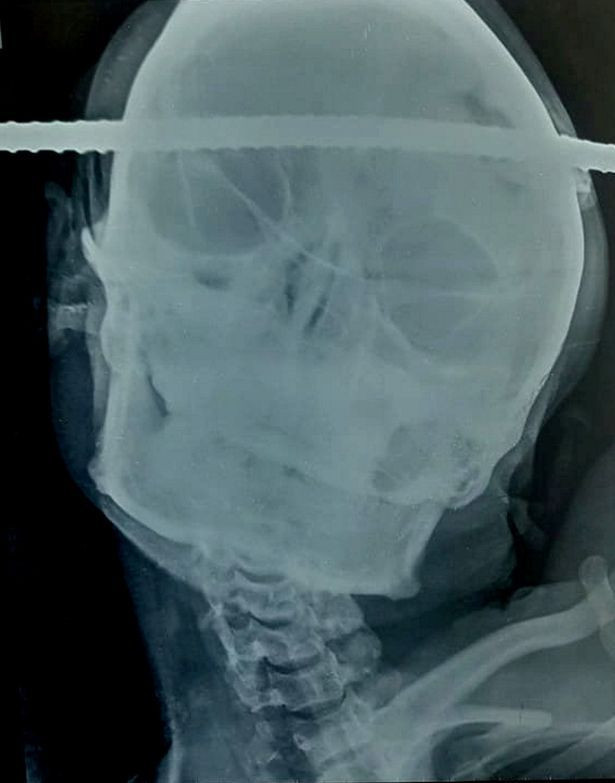

HİNDİSTAN'ın Balaghat şehrinde 21 yaşındaki Sanjay Bahe isimli inşaat işçisinin başına demir çubuk saplandı. Korkunç olay ise bakın nasıl gerçekleşti.

Korkunç olay Hindistan'da meydana geldi. 21 yaşında inşaat işçisi olan Sanjay Bahe şantiyede çalıştığı sırada dehşeti yaşadı ve başına demir çubuk saplandı. Demir çubuk beyninin sağ temporal bölgesinden sol ön bölgesine geçip kafa tasını deldi.

Orta Hindistan’daki Balaghat şehrinde yaşayan genç adam şantiyede çalıştığı sırada bir kuyuya düştü. Kuyuya düştükten sonra demir çubuk genç adamın kafa tasına saplandı. En kısa sürede yakınındaki BJ Hastanesine kaldıran genç adam 90 dakika süren zorlu bir ameliyata alındı.

Dr Pramod Giri'nin önderlik ettiği bir beyin cerrahı ekibinin yaptığı zorlu ameliyat sonrası demir çubuk çevrede herhangi bir kanama veya yaralanmaya neden olmadan güvenli bir şekilde çıkarıldı.

Genç adam mucizevi bir şekilde hayatta kalmayı başarırken Dr Giri şu açıklamayı yaptı "Bu gibi durumlarda hastaya anestezi vermek zordur. Operasyon sırasında beyinde hayati kanalları korumak için entübasyonu konumlandırarak doğru müdahale yaptık.